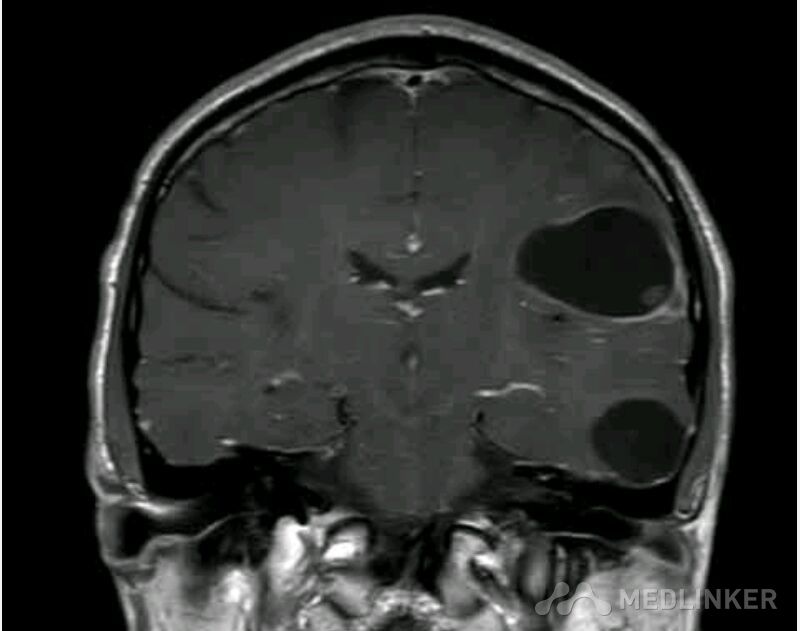

脑囊虫病高清影像资料分享

脑囊虫病经典资料